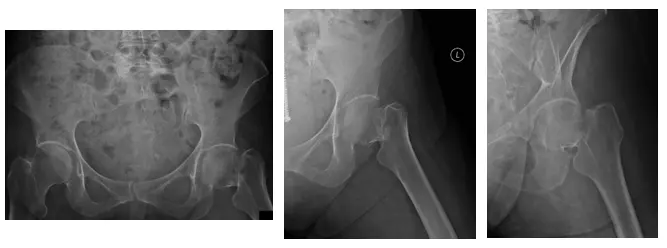

Las radiografías muestran una luxación del THA izquierdo